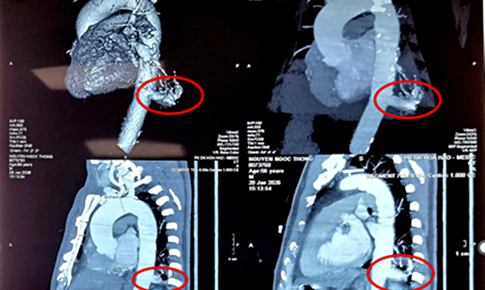

Bệnh trẻ em - 21/11/2024 11:19SKĐS - Dị dạng lồng ngực còn gọi là ngực hình phễu hoặc lõm xương ức. Bệnh phổ biến ở nam giới hơn nữ giới. Nếu không phẫu thuật sớm, bệnh có thể gây ra các triệu chứng ảnh hưởng đến chức năng tim phổi, đồng thời gây ảnh hưởng tâm lý đến cha mẹ và trẻ.